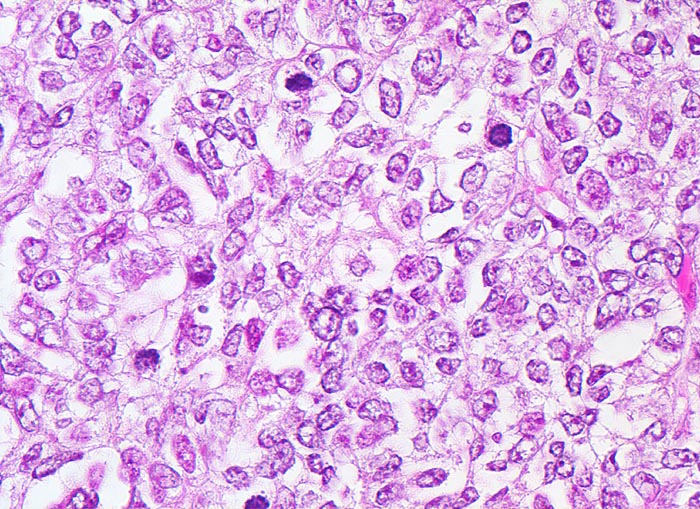

PathoPic – image database / PathoPic ID 4446 - wenig differenziertes endometrioides Adenokarzinom

wenig differenziertes endometrioides Adenokarzinom

Solider Tumorzellverband. Die vesikulären (bläschenförmigen) Kerne sind polymorph und hyperchromatisch. Die Kernmembranen sind unregelmässig. Die Kern-Zytoplasmarelation ist erhöht. Mehrere Mitosen.

Exophytischer, in das Uteruscavum hineinragender, weicher fokal hämorrhagischer Tumor ausgehend von der Uterushinterwand. Das Tumorgewebe infiltriert die innere Hälfte des Endometriums.

Postmenopausale Blutung. Diagnose eines endometrioiden Adenokarzinoms in der Corpuskurettage. Daraufhin Hysterektomie, Adnexektomie und Lymphadenektomie.

Histologie

400